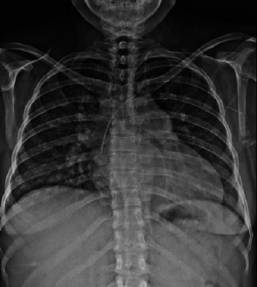

Puérpera de 32 años con antecedente de dos embarazos previos complicados. El primero, con preeclampsia severa con muerte del feto in utero por causa desconocida a las 38 semanas de gestación; el segundo embarazo cursó normoevolutivo durante la gestación hasta el expulsivo donde se realizó un parto instrumentado con fórceps. Inició siete días previos a su ingreso con edema de miembros pélvicos no doloroso, ascendente, caliente, blando; a las 24 horas se agregó cefalea parietal bilateral, pulsátil, con intensidad 8/10, acompañada de náusea con vómito de contenido gastrobiliar y disnea de pequeños esfuerzos. Acudió a facultativo, quien detectó cifras tensionales de 130/80 y la refirió a un hospital de tercer nivel. Se internó en el Servicio de Materno-Fetal con sospecha diagnóstica de trombosis venosa profunda. Cursó con deterioro súbito de la función pulmonar manifestado con hipoxemia severa; requirió de ventilación mecánica invasiva por desarrollo de edema agudo pulmonar; por taller hemodinámico se documentó falla cardiaca con datos de disfunción diastólica, que precisó de inotrópico y vasopresores. Se recibió en la terapia intensiva sedada con RAMSAY 5, eutérmica (temperatura: 37.5 oC), taquicárdica (122 latidos/minuto), hipotensa (89/47 mmHg), aún con apoyo de vasopresina y norepinefrina, manteniendo presiones medias > 70 mmHg. Con precordio hiperdinámico con levantamiento para esternal bajo, se palpó chasquido de cierre pulmonar. Ruidos cardiacos disminuidos con reforzamiento del segundo ruido y soplo holosistólico II/VI en el foco mitral, sin galope o frote pericárdico; trazo electrocardiográfico: con fibrilación auricular de respuesta ventricular alta (Figura 1), taller hemodinámico con patrón hiperdinámico. Con soporte ventilatorio mecánico invasivo, campos pulmonares hipoventilados con estertores en velcro, abdomen globoso con aumento del timpanismo, peristaltismo disminuido, con oliguria en 0.3 cm3/kg/hora. Se realizó una radiografía de tórax con infiltrado en alas de mariposa, además de cono pulmonar prominente, elevación del hemidiafragma derecho (Figura 2). Laboratorios: antiestreptolisinas 53 UI/m, factor reumatoide 20.5, procalcitonina 4.120 ng/mL, CPK 281 µ/L, CKmb 29 U/l, dímero D 9898 ng/mL, péptido natriurético cerebral: 863.90 pg/mL, velocidad de eritrosedimentación y proteína C reactiva aumentadas. Se realizó interconsulta con el Servicio de Cardiología, quien llevó a cabo ecocardiograma transtorácico, con estenosis valvular mitral con área de 1.2 cm (Figura 3) y gradiente transvalvular de 36 mmHg, con probable etiología reumática. Hipertensión arterial pulmonar severa con presión sistólica del ventrículo derecho (PSVD) de 83 mmHg y función sistólica biventricular conservada; dilatación del ventrículo derecho con excursión sistólica del anillo tricuspídeo (TAPSE) de 23 mm; no se pudo evaluar de forma adecuada el estado de la válvula aórtica, solo se encontró gradiente ligeramente incrementado, que se puede atribuir a hiperdinamia. Sin signos clínicos de tromboembolia pulmonar, fracción de expulsión del ventrículo izquierdo (Fevi) de 80% (Figura 4). El Servicio de Nefrología integró el diagnóstico de lesión renal aguda prerrenal AKIN III y el Servicio de Neumología corroboró ausencia de datos de trombosis pulmonar, aun con la elevación del dímero D (9898). Se instauró manejo farmacológico con vasodilatadores dinitrato de glicerilo, inotrópico (levosimendam), morfina, diuréticos, betabloqueador, sildenafil (para manejo de hipertensión pulmonar) y terapia de sustitución renal precoz (hemodiálisis) de urgencia para manejo de sobrecarga hídrica. La paciente evolucionó favorablemente a la terapéutica a base de metas de paciente crítico. Se inició el retiro de aminas vasopresores, sildafenil e inotrópico a las 72 horas, sin repercusión hemodinámica, con posterior retiro de la ventilación mecánica al cuarto día de resolver el edema pulmonar. Con mejoría hemodinámica, se realizó una nueva valoración por parte del Servicio de Cardiología, quien la catalogó como estenosis mitral moderada y decidió control ambulatorio. La paciente fue egresada de terapia al octavo día de internamiento, sin repercusión hemodinámica o fallas orgánicas. A la semana inició consulta de forma ambulatoria en el Servicio de Cardiología para programar su tratamiento quirúrgico: valvuloplastia percutánea mitral por balón.